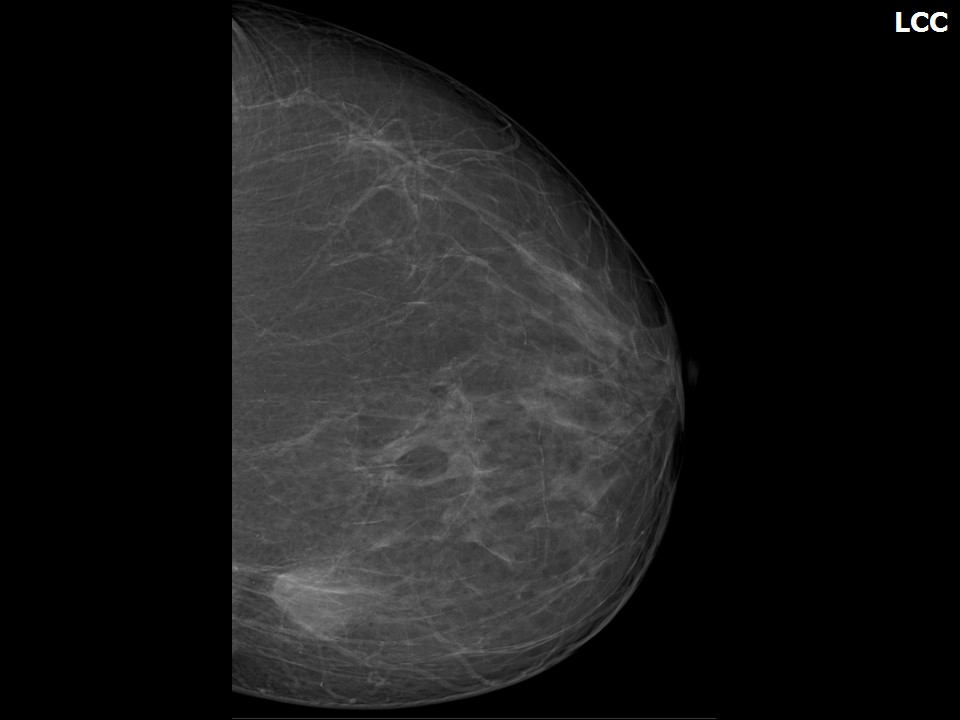

Феномен гипердиагностики в маммографии: примеры и иллюстрации

Раздел: Образы вокруг